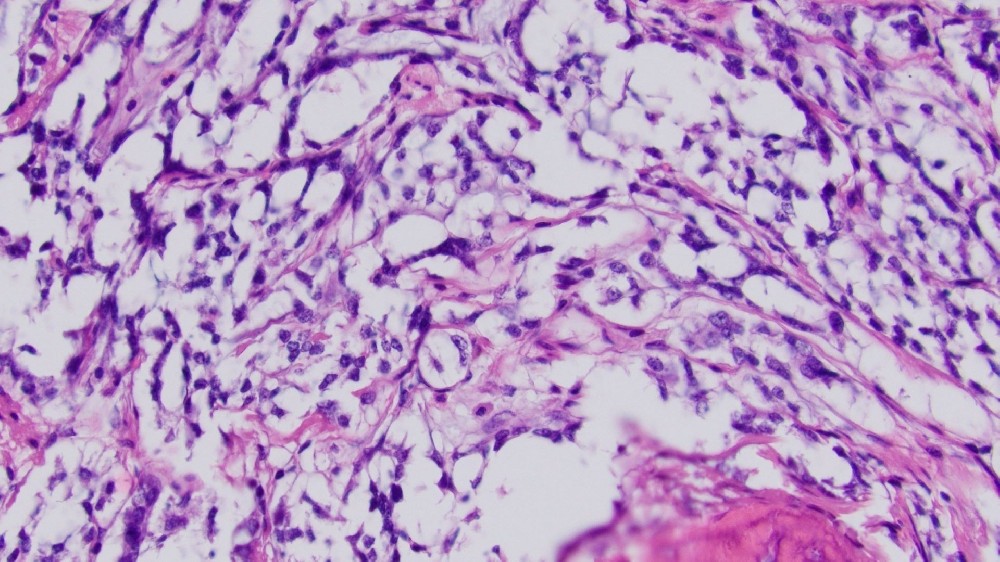

胃腸道基質腫瘤 (GIST) 是一種罕見的癌症,特徵是胃腸道 (GI) 出現異常細胞,主要來自於稱為 Cajal 間質細胞的專門神經細胞。這些細胞調節消化運動,對腸道健康起著關鍵作用。GIST 主要影響胃和小腸,但也可能出現在消化系統的任何部位。

GIST 腫瘤通常是由負責編碼受體酪氨酸激酶 (RTK) 的 KIT 或 PDGFRA 基因突變所引起。突變後,這些蛋白會不受控制地活化,造成細胞過度生長和分裂。對這些生物因素的全面瞭解可增強病患的能力,並設計出具針對性的治療方法。